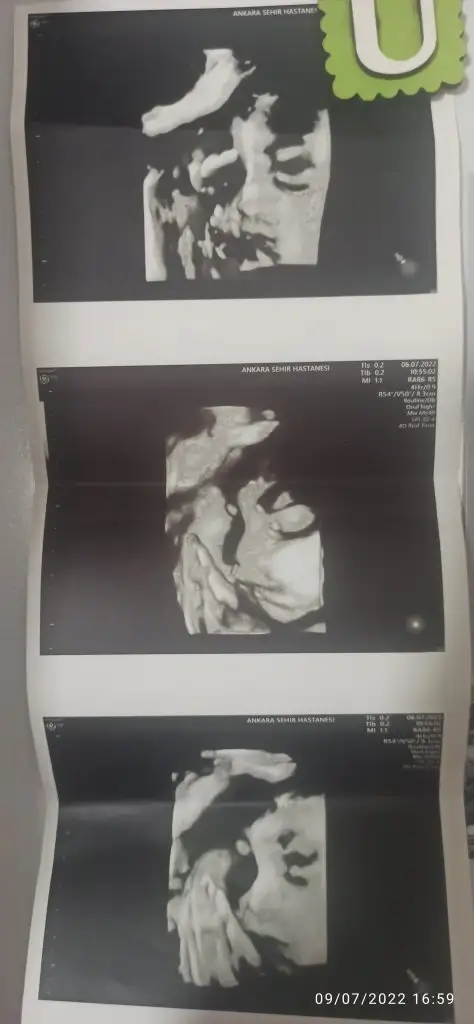

Bizde çarşamba günü kontrole gittik. Aslında 4 hafta sonra gel demişlerdi kasılmalarım başlayınca ve bayram tatili de araya girince dayanamadım gittim. Şükür iyiyiz.29+0 haftalıkdı gittiğimde 1400 gram olmuş kızımın kilosu boyuda 39.2 cm kasılmalardan bahsedince idrar tahlili ve idrar kültürü istedi doktorum önceden aile hekiminde kan tahlili var deyince kanı istemedi bu sefer. Bizim kız parmak emmeye başlamış 🧿😊 parmak emerken pozunu yakaladı doktorum. Kasılmalar var denincede nstye gönderdi . Nst 30 -40 arası sancım çıktı düzenli olarak görünce tekrar istedi susuzmusun diye sormuştu açıkçası pek su içemeden gitmiştim sabah. 1 litre su içip tekrar girdim nstye bu sefer şükür pek sancı çıkmadı.3 hafta sonra gelmemi bolca su içip magnezyum içmemi söyledi. Bundan sonra sürekli nstye gircez galiba. 32 hafta biran önce gelsede gitsem tekrar artık gün saymaya başladım sağlıcakla kavuşalım diye doğum için günüm belli olsun diye.

Yaaaa yerimmm o nasıl bir poz maşallah canım böyle güzel pozlar günümüzü şenlendiriyor 🥰 çok bişey kalmadı bı agustos ayı var önümüzde sonu gibi de dogumlarimiz başlar diye düşünüyorum sağlıkla gelsin meleklerimiz ❤️